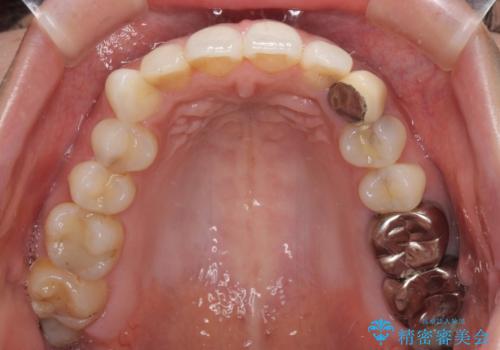

- 前歯の保険のかぶせものをセラミックに替えたいと来院された患者様です。

保険のかぶせもの特有の変色や縁の金属色、歯根が一部見えている点が気になるとのことでした。

土台の金属を除去してファイバーコアによる土台植立を行い、オールセラミッククラウンにて補綴することとしました。